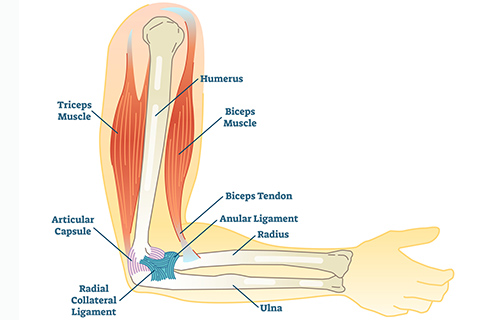

Arm Injuries

Arm Injuries